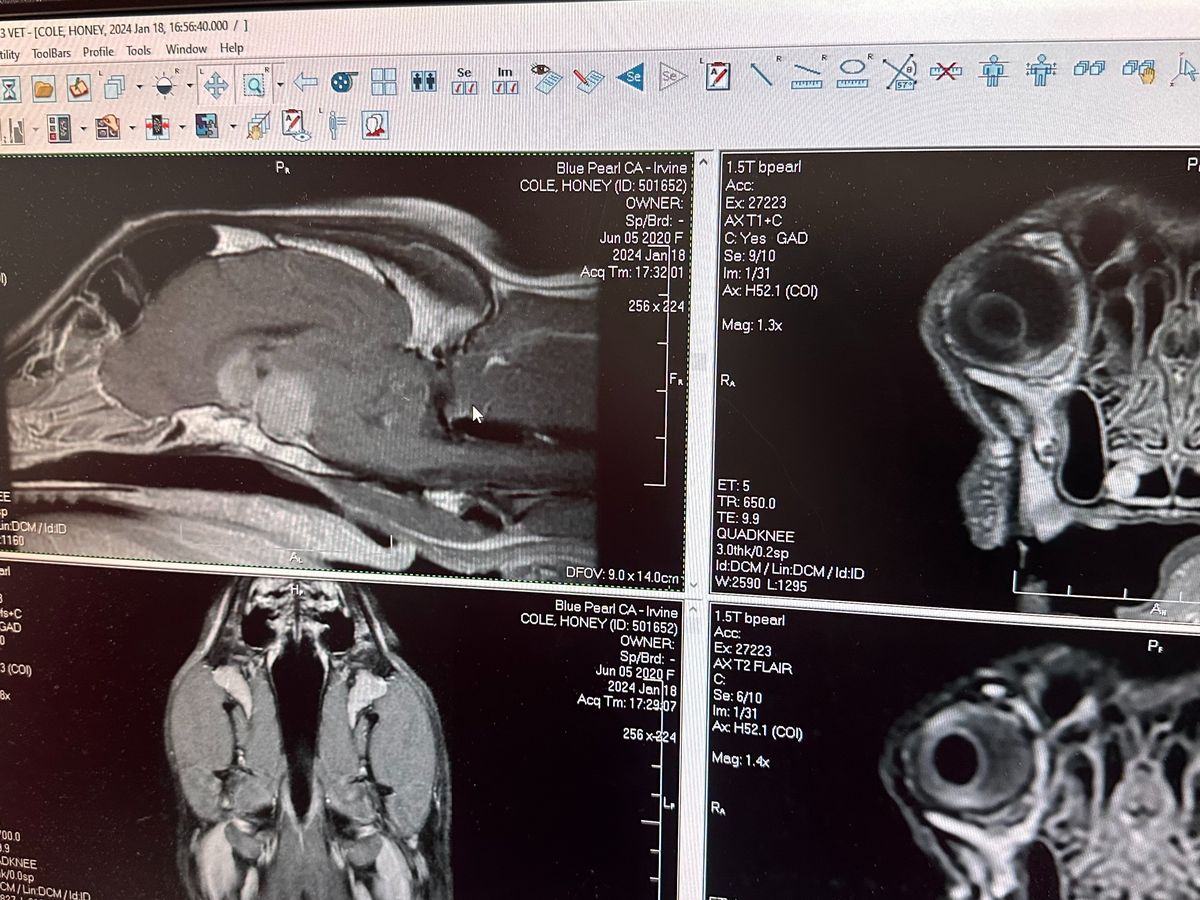

Hello my name is Kaylan Cole and after much contemplation, we've decided to reach out through this GoFundMe in the hope of receiving assistance as we face the overwhelming challenge of our beloved Honey's recent diagnosis. On January 18th, our three-year-old Border Collie Mix, Honey, was diagnosed with an incredibly rare pituitary macroadenoma tumor, leaving us with no option for a cure other than radiation.

This devastating news came upon us swiftly, and Honey, who is not just a pet but a cherished member of our family, has become the center of our concern. Desperate to ensure she has the chance for more healthy years, we're exploring every avenue possible, starting with radiation. The uniqueness of her case has left doctors astonished – they've never encountered a tumor of this size in a dog so young.

Attached are some photos of her as well as her MRI scan with the tumor.